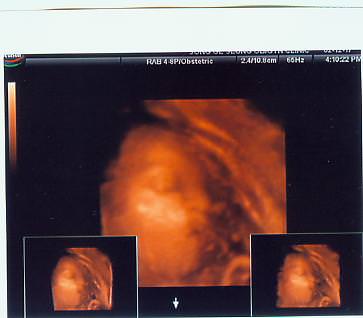

못생긴 제얼굴 올려요~